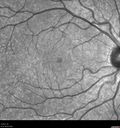

25 year old man with 1 week vision loss 20/16 OD 20/100 OS - CRVO

Heterozyrous for Factor V Leiden - Required 3 years of Lucentis - VA improved to 20/30. Able to stop therapy